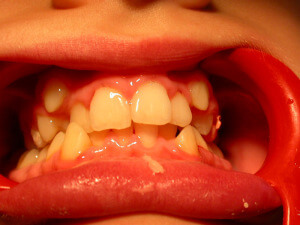

Interceptive Orthodontics

There are ways to prevent orthodontic problems and avoid braces. It’s essential to check our children early and on a regular basis, to avoid teeth crowding, discontinue a bad oral habit, or in order to guide favorably the facial and dentoalveolar development.